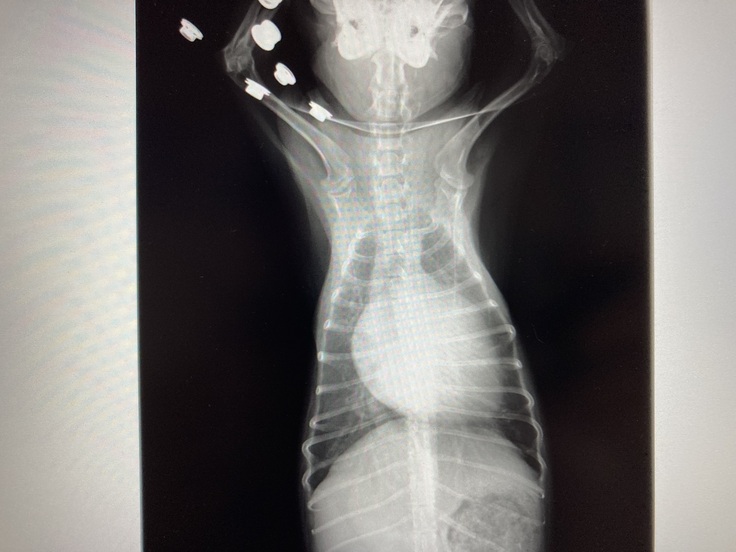

▼現在のココのレントゲンとエコー写真

心臓が大きく肥大していて

逆流も多く、かなり悪い状態で

余命6〜9ヶ月と宣告されました。